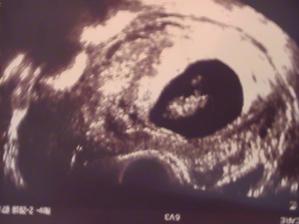

9tt 🙂

A zase sme o kúsok väčší..máme už 2 cm 🙂🙂